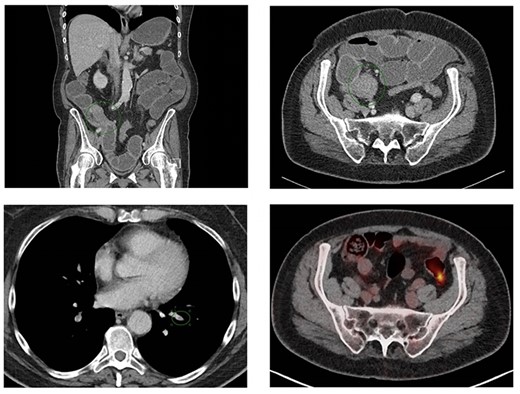

Despite continuous use of anticlotting agents, it was impossible to remove the inferior VCF twice (5 and 22 days postoperatively) due to thrombosis adjacent to the VCF. Eight days postoperatively, the patient had progressive pain in the left lower abdominal quadrant, stoma bleeding, tachycardia, hypotension and a hemoglobin level of 5.8 g/dL (3.6 mmol/L), WBC count of 36.2*10E9/L and CRP level of 32.9 mg/L. CT angiography revealed a rectus sheath hematoma with continuation into the small pelvic cavity without active blush, while heparin was administrated (Fig. 4A). Intravenous heparin was switched to therapeutic subcutaneous nadroparin and because of an infected hematoma suspicion, piperacillin/tazobactam was given. Ca15-3 was 49 and 38 kU/L (reference range 0–30 kU/L) at the 21st and 24th postoperative day, respectively.

CT scans performed at the 8th (A) and 25th (B) postoperative day showed a decreasing rectus sheath hematoma (green ellipse), increasing free intraperitoneal fluid (green asterisk) and blood clot progression with small air configuration near the VCF (green arrow). Also, enlargement of the blood clot at the level of the VCF, an increase in pleural fluid, bile duct dilatation and an increase in right-sided hydronephrosis were observed caused by further metastatic disease and paraneoplastic syndrome.

Due to therapy-resistant pulmonary embolisms, recurrent glucose level swings, progressive renal insufficiency and the indication for palliative hormonal therapy, the patient was transferred to the internal medicine ward for further treatment. After clinical deterioration, an abdominal CT scan 25 days postoperatively showed a gradual decrease of the rectus sheath hematoma with concomitant increase in free intraperitoneal fluid presumably following perforation of the hematoma and new abnormal findings as a consequence of further metastases and the paraneoplastic syndrome (Fig. 4B). Therefore, maximum conservative palliative treatment was instituted, patient died shortly thereafter, and no autopsy was performed.